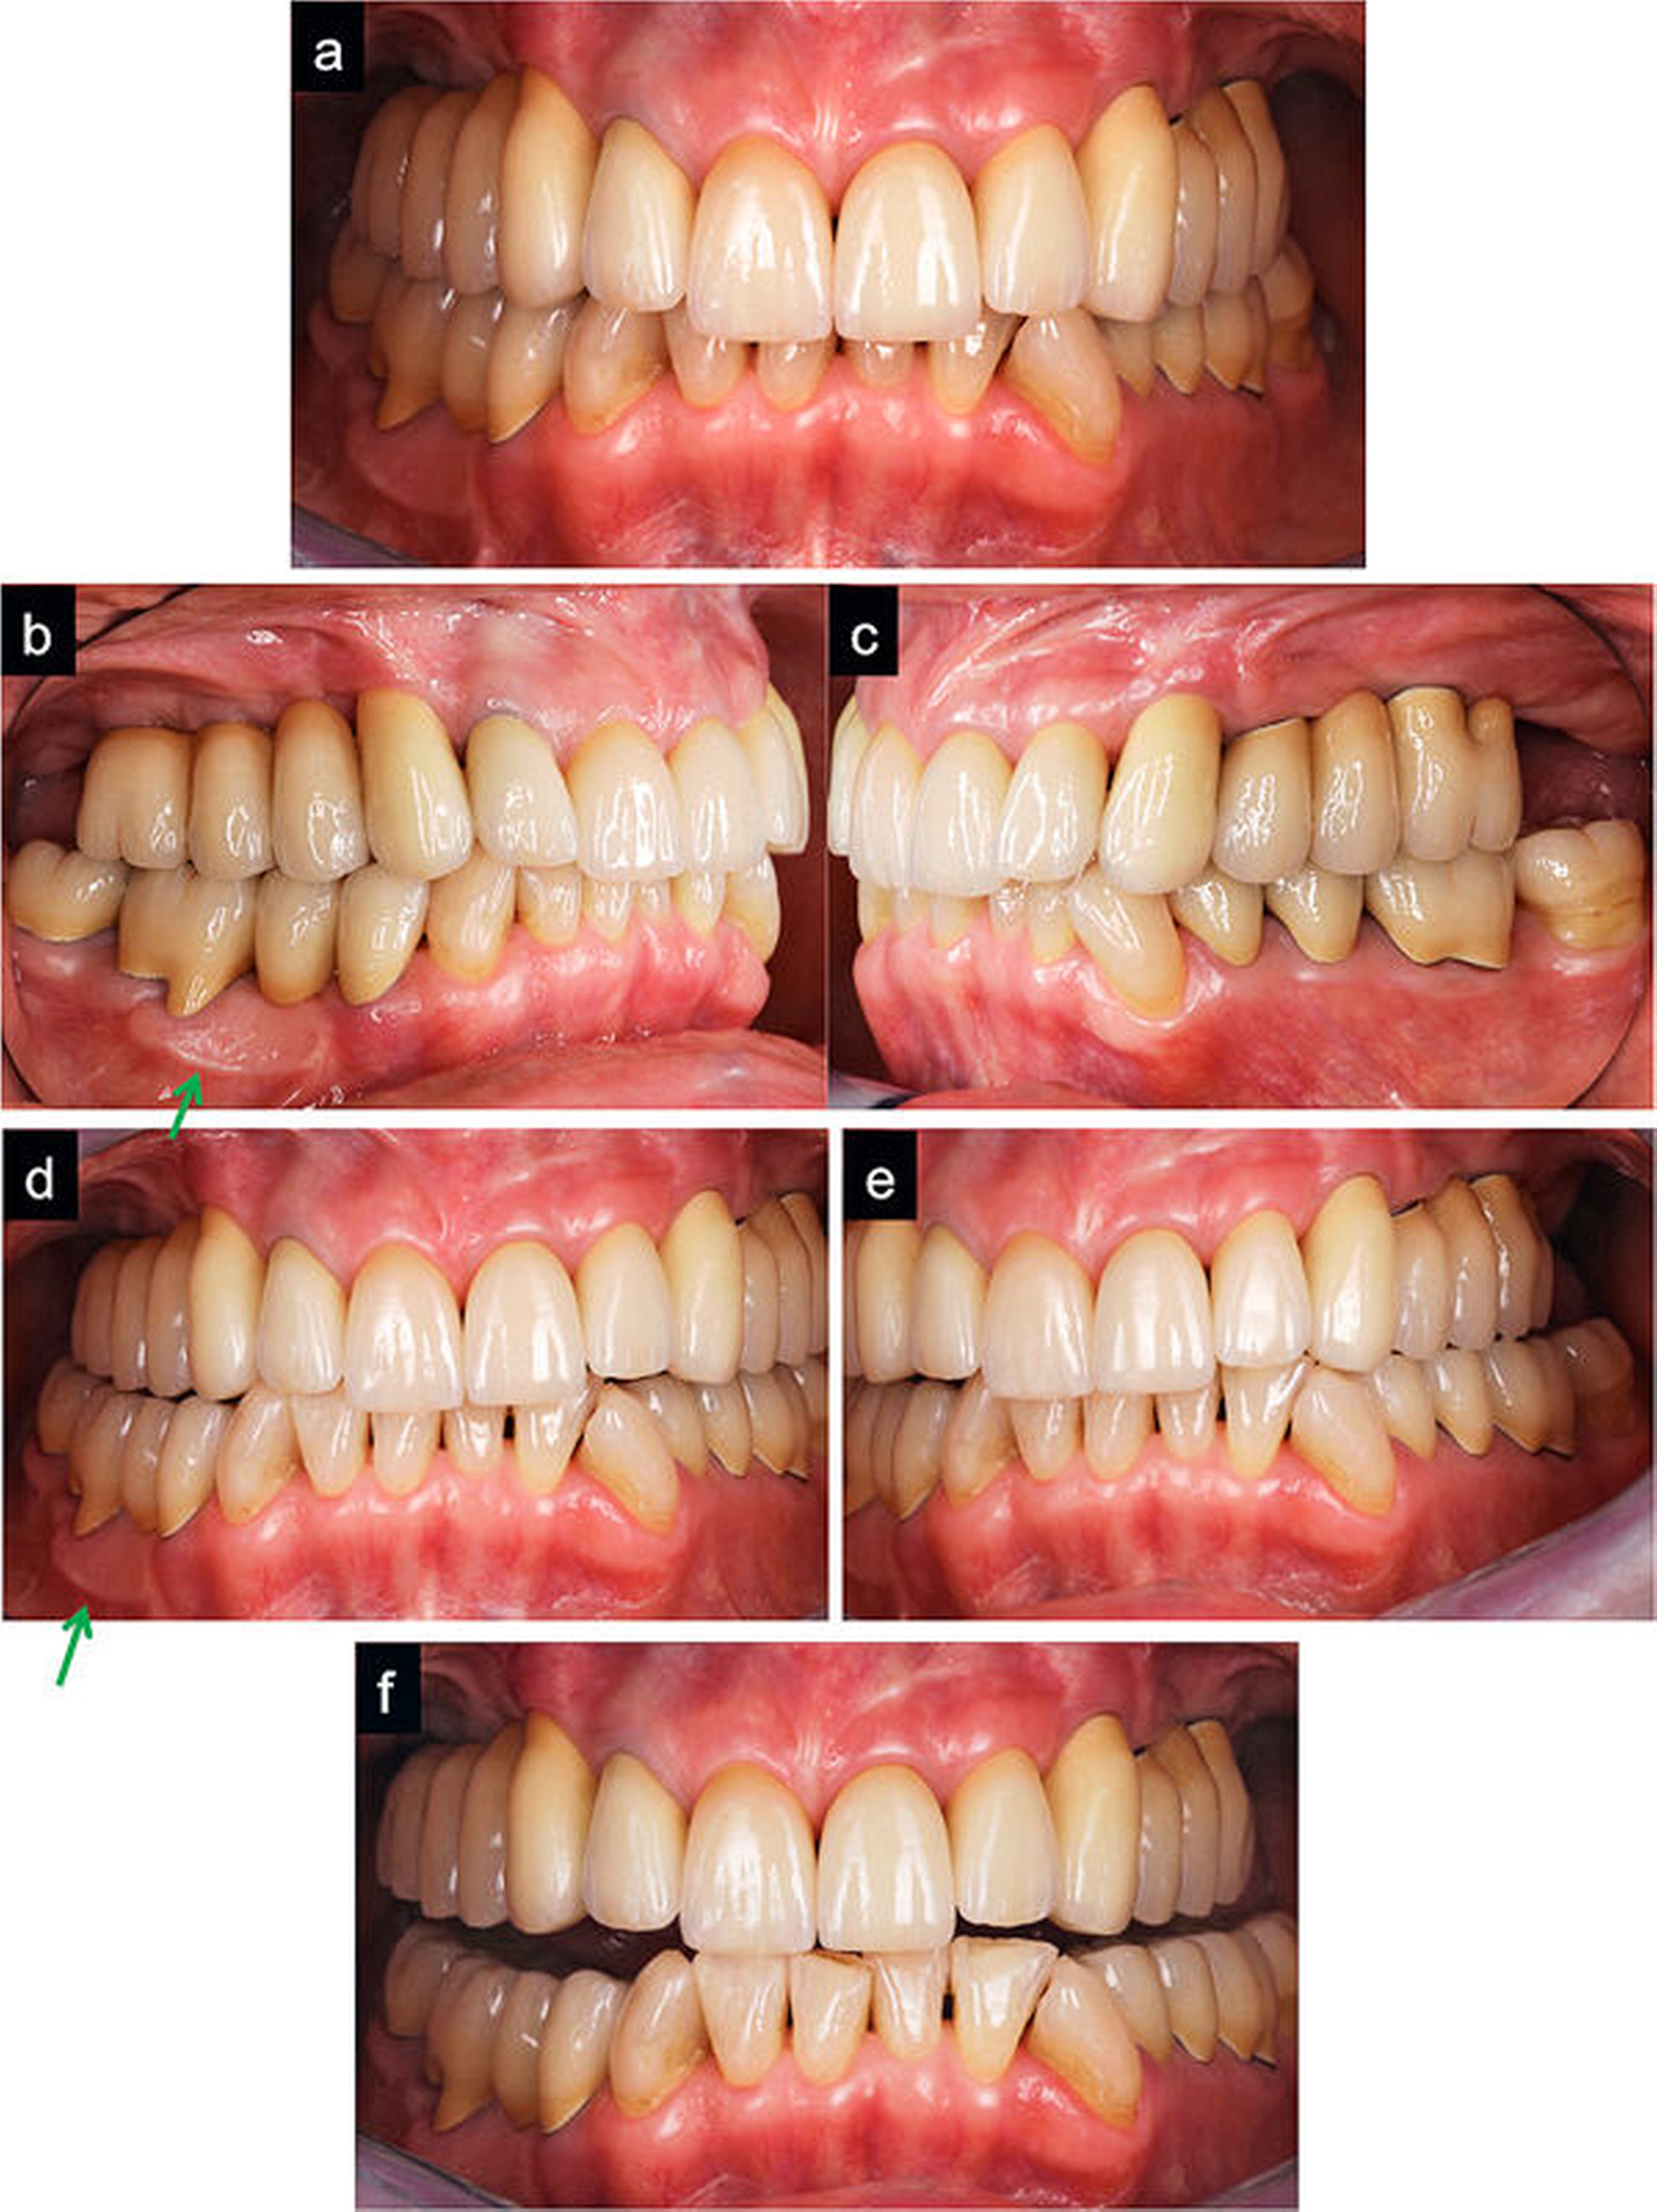

Die Abbildungen 3a bis 3g zeigen die intraorale und die röntgenologische Situation nach den beschriebenen Vorbehandlungen mit und ohne Interimsversorgung. Der Zahn 23 ist zu diesem Zeitpunkt erfolgreich wurzelbehandelt und von der Interimsprothese noch bedeckt.

Im nächsten Schritt wurde die Oberkieferfrontzahnsituation bearbeitet, der Eckzahn 23 aufgebaut und mit einem Provisorium versorgt und die Interimsprothese umgestaltet. Zur Veranschaulichung wurden die ästhetischen Korrekturmöglichkeiten in der Front via direktem Mock-up an den Zähnen 11 und 21 visualisiert. Dabei wurde der Zahn 21 mit einem schwarzenFilzstift inzisal optisch gekürzt. Zervikal wurde er dafür mit einem einfachen Anbau mit Komposit „verlängert“, während an Zahn 11 lediglich im inzisalen Bereich Komposit aufgetragen wurde, um die sagittal abweichende Angulation der Zähne auszugleichen (Abbildungen 4a bis 4d).

In den Abbildungen 5i bis 5j ist eine deutliche Harmonisierung der ästhetischen Erscheinung zwischen dem Zustand vor und nach Versorgung mit dem Provisorium anhand des idealisierten Wax-ups zu erkennen.

Nachdem nun die beiden mittleren Schneidezähne inzisal auf eine symmetrische Länge und Form eingestellt wurden (Abbildung 6a), mussten die Zahnlängen in zervikaler Richtung harmonisiert werden. Hierfür wurde eine minimalinvasive chirurgische Kronenverlängerung nach dem Konzept von Schwenk und Striegel durchgeführt (Abbildungen 6b bis 6d), die sich für kleine Korrekturen in der ästhetischen Zone sehr gut anbietet, da sie sehr schonend und ohne jegliche chirurgische Lappenbildung durchzuführen ist und eine schnelle Heilung der Gewebe ermöglicht (Abbildungen 6e und 6f). Als weitere Maßnahmen seien noch die Transplantation keratinisierter Gingiva in regio 45–46 mittels FST aus dem rechten Gaumen (Abbildung 6f) und die Implantatfreilegung erwähnt.